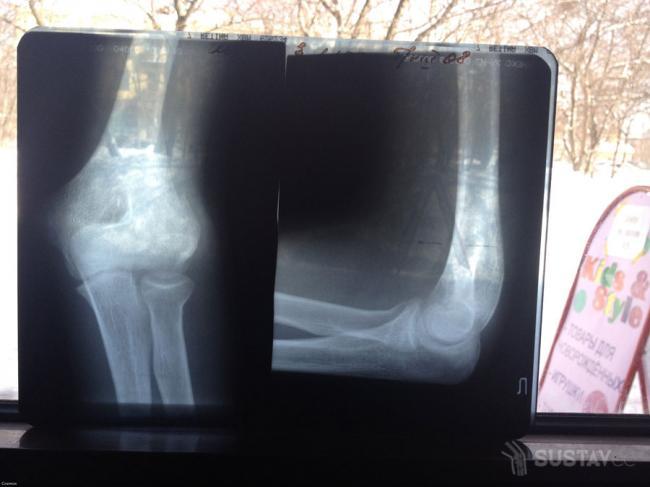

- Назначается рентгеновский снимок, чтобы исключить перелом и посмотреть в каком состоянии находится хрящевая ткань.

- Обязательным является рентген поврежденного сочленения, позволяющий выявить его аномалии.